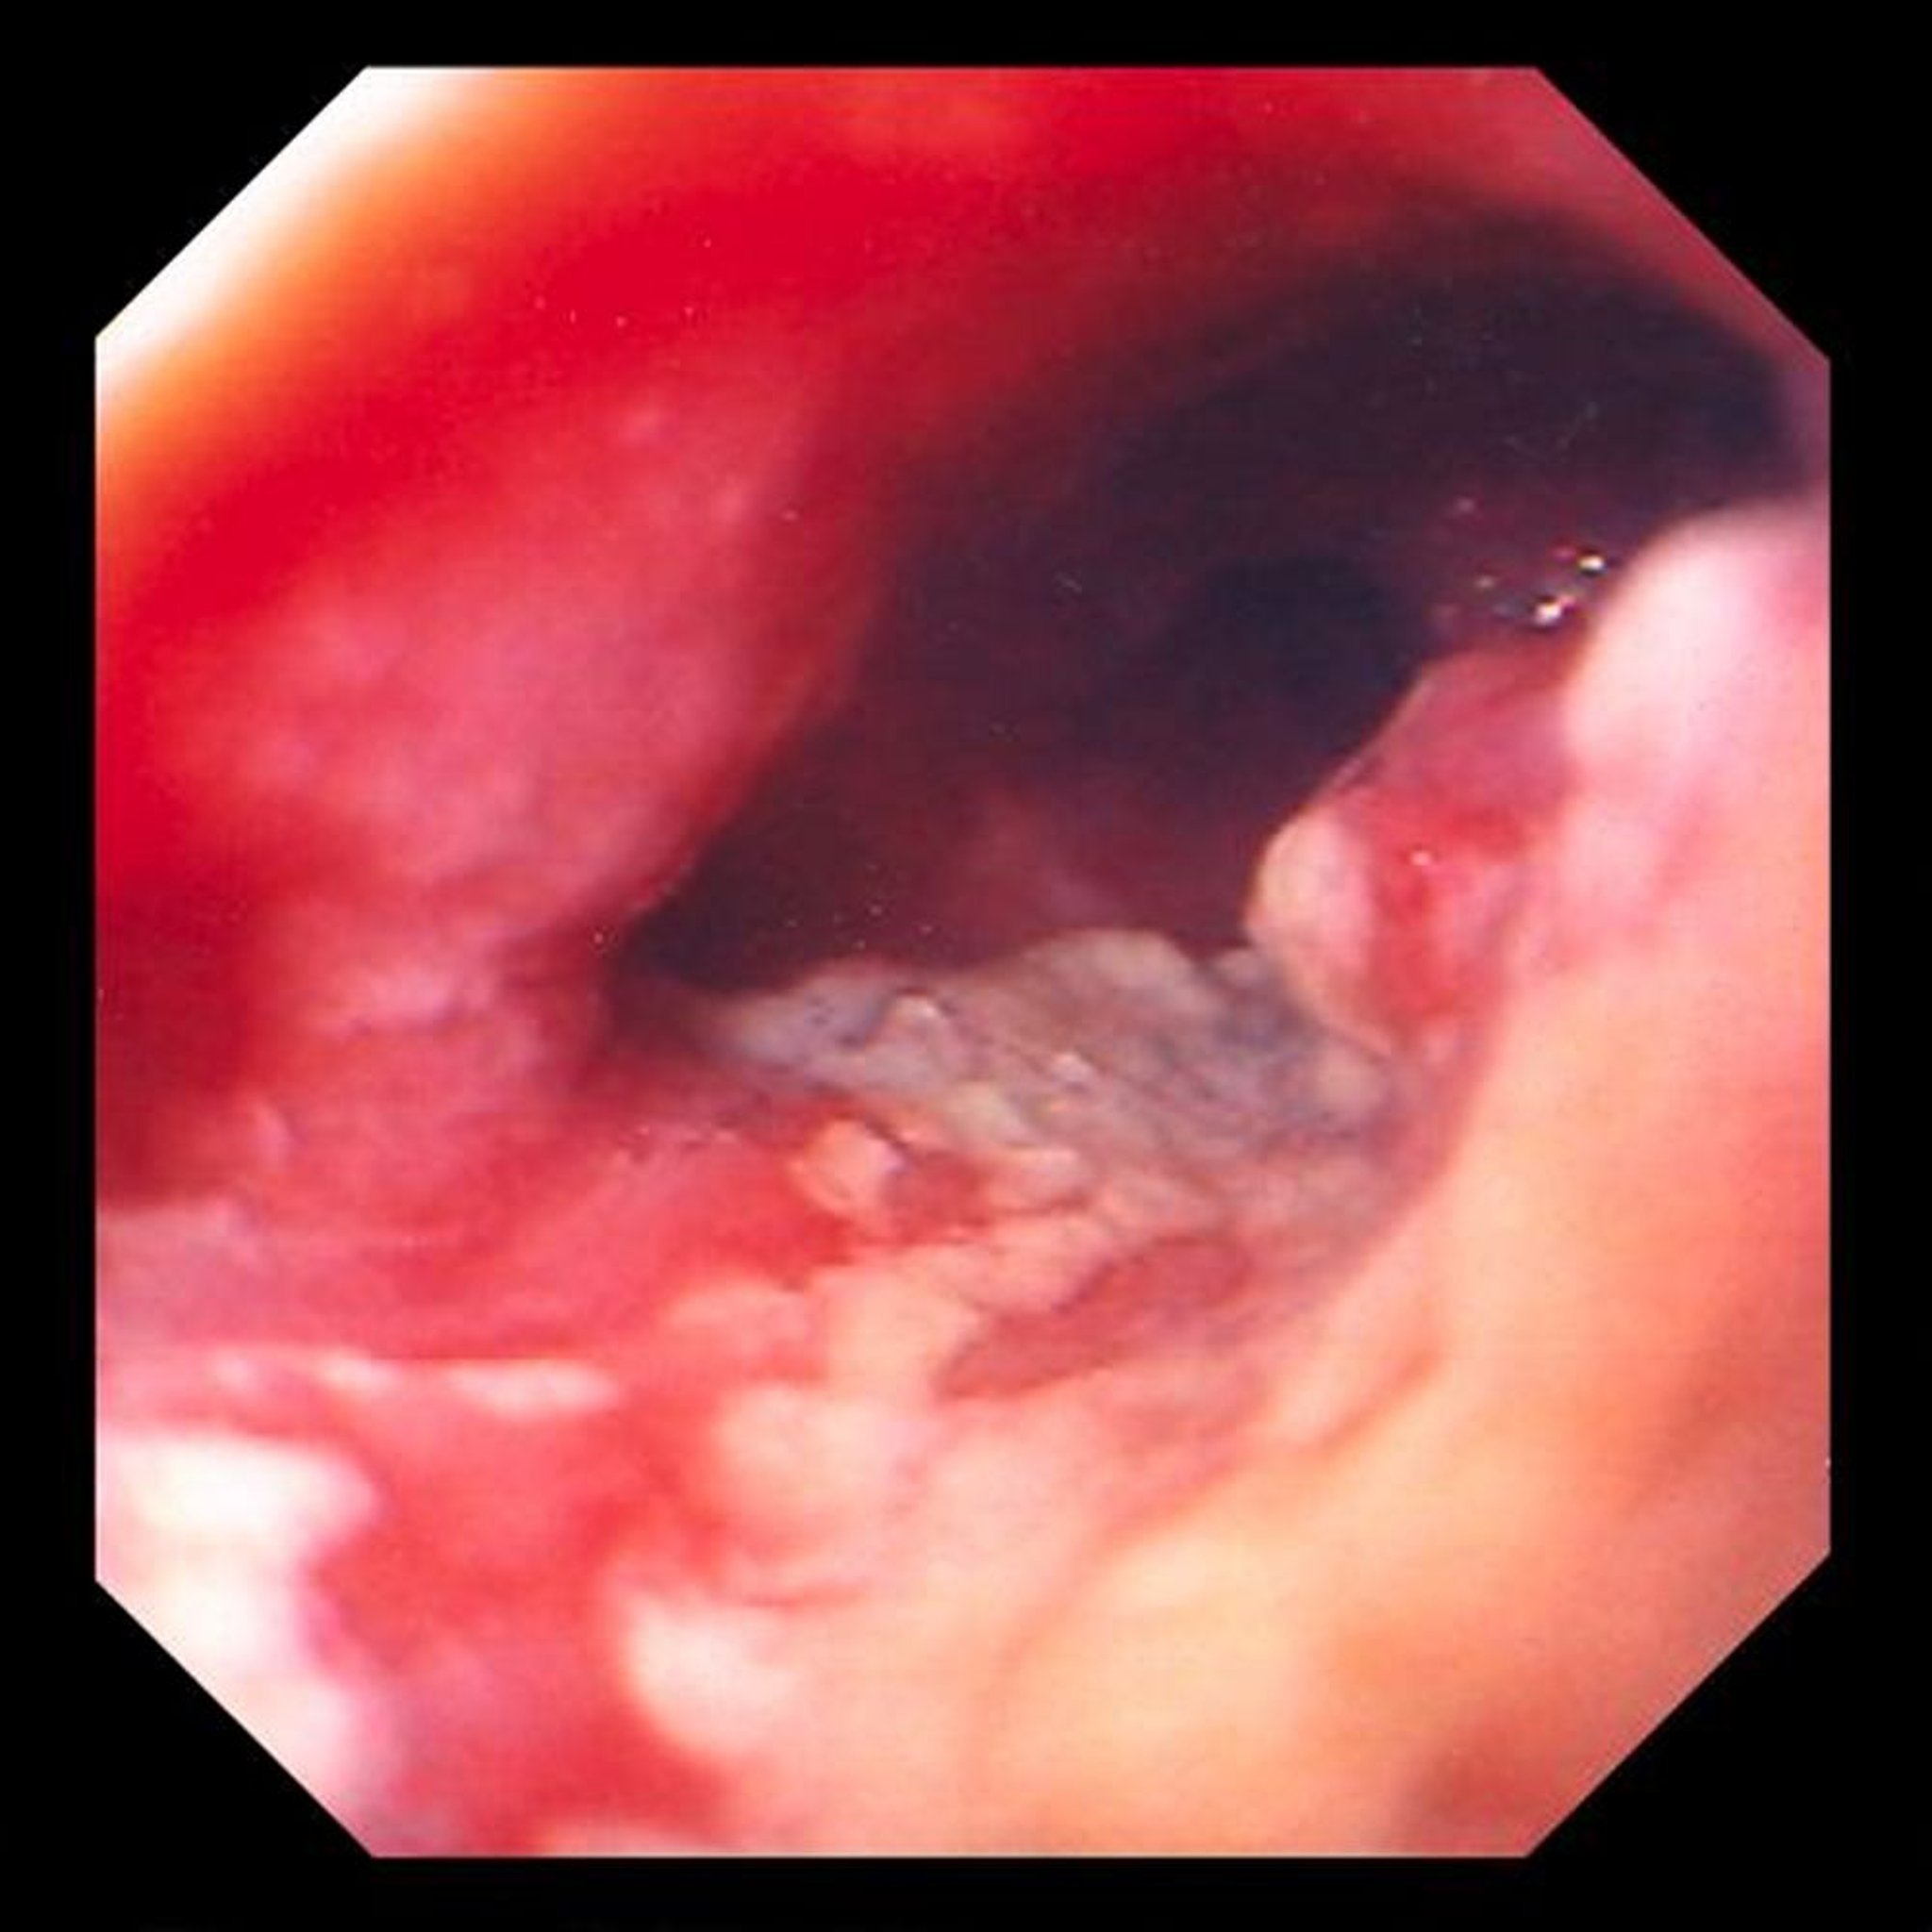

Adenocarcinoma dell'esofago

Questa immagine mostra un tumore ulcerato e costrittivo situato nell'esofago distale, che è altamente indicativo di un adenocarcinoma derivante da cambiamenti colonnari metaplastici (esofago di Barrett).

Image provided by David M. Martin, MD.